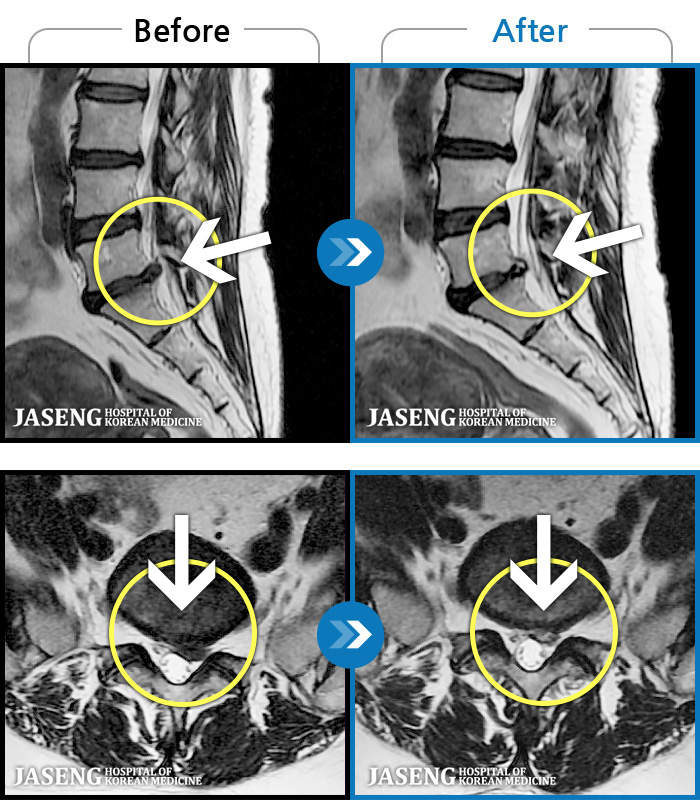

1,240 MRI ũ ʸ Ȯϼ.

| [뱸] 19.11.28~25.05.06